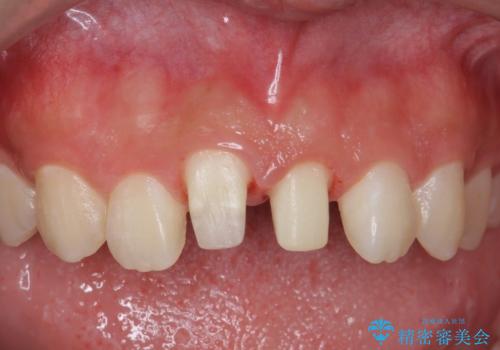

前歯の角度や歯ぐきのラインに差が大きかったため、やむなく神経をとり、歯ぐきの手術を行い出来るだけ歯ぐきのラインを整えるようにしました。

手術をしなければ左上1番の歯ぐきのラインは左上2番よりも下にきてしまい、長さの短い歯になってしまうところでした。

- 31万円(ジルコニアクラウン(スタンダード)10万円x2、仮歯 1万円x2 ファイバーコア 2万円x2 ジンジペクトミー 5万円)費用は治療当時の料金となります

笑っても大きく歯ぐきが見える方ではなかったので、歯ぐきのラインが目立つことはなかったです。

手術をしなければ左上1番の歯頚ラインは左上2番よりも短い位置になっていたため、歯自体の長さが不自然なほど短くなってしまったと思います。